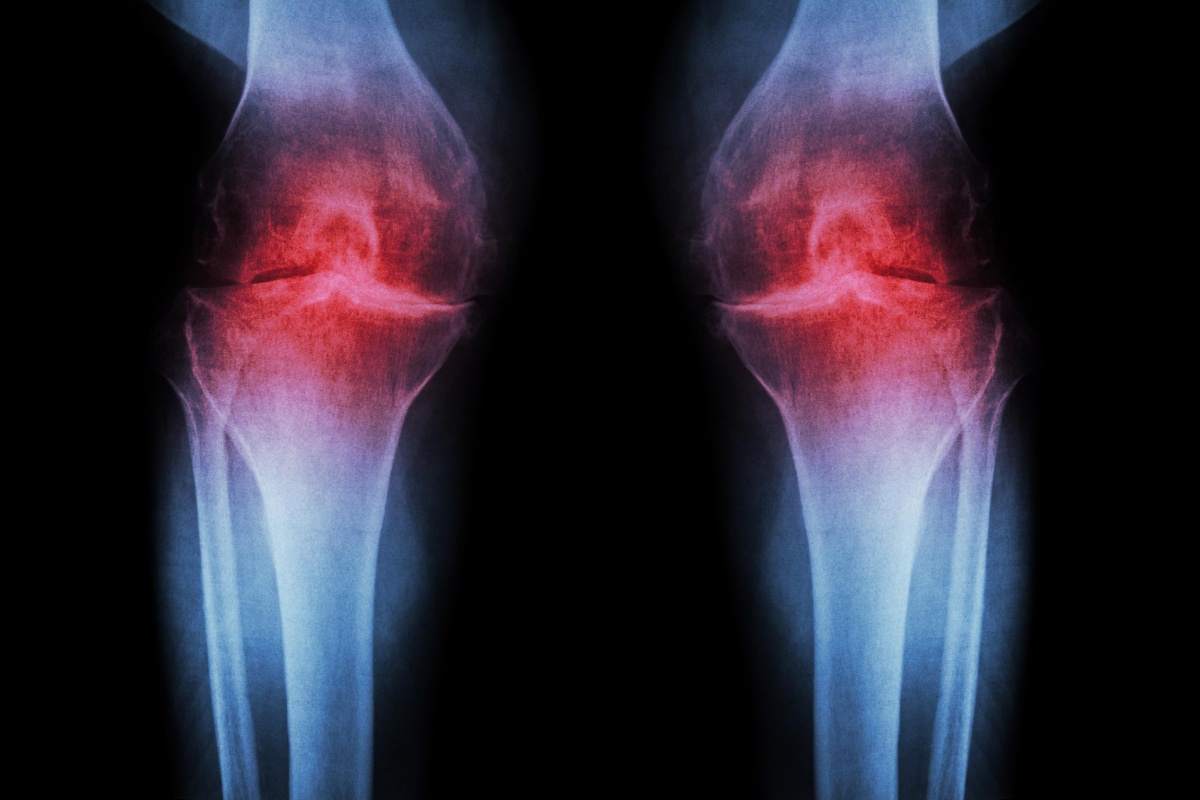

Znanstvenici s Medicinskog fakulteta Sveučilišta Stanford izvijestili su o tretmanu koji blokira protein povezan sa starenjem, čime se obnavlja hrskavica koja se prirodno troši u koljenima. Ovo otkriće nudi nadu milijunima ljudi jer tretman koji se ubrizgava ne samo da obnavlja hrskavicu, već i zaustavlja razvoj artritisa nakon ozljeda koljena, poput puknuća prednjeg križnog ligamenta (ACL), koji su česti kod sportaša.

Ljudsko tkivo koljena prikupljeno tijekom operacija zamjene zglobova također je pozitivno reagiralo na tretman. Uzorci su počeli stvarati novu hrskavicu koja funkcionira normalno, što ukazuje na to da bi se hrskavica izgubljena starenjem ili artritisom jednog dana mogla obnoviti lokaliziranom injekcijom ili oralnim lijekom. To bi potencijalno moglo eliminirati potrebu za složenim operacijama zamjene koljena ili kuka.